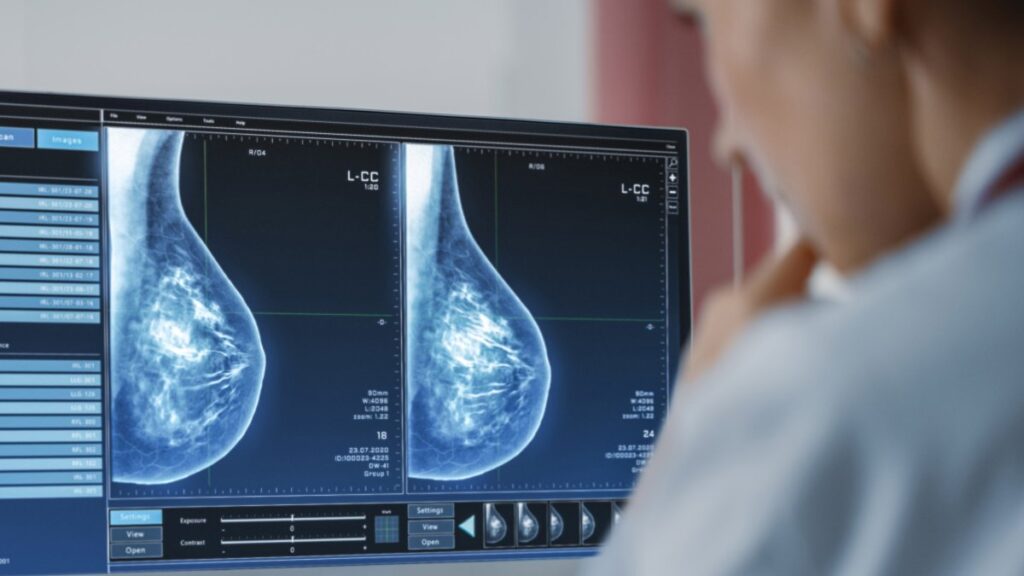

Eso es antes de lo que el panel independiente de expertos recomendó anteriormente: la última guía, de 2016, sugirió exámenes de detección bienales a partir de los 50 años, pero señaló que las mujeres de 40 años podían hablar con su médico acerca de hacerse exámenes de detección, especialmente si tenían antecedentes familiares de cáncer de mama. Los exámenes de detección generalmente involucran una mamografía, que es una imagen de rayos X del seno.